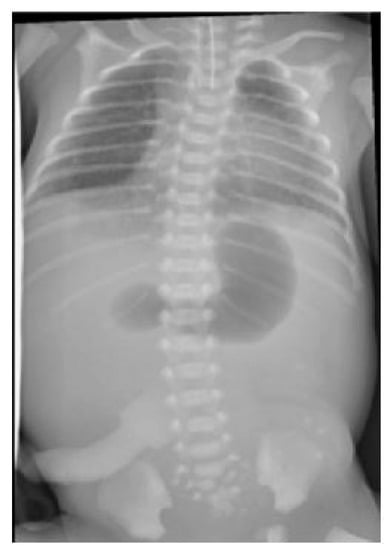

An abdominal and chest radiograph confirmed the diagnosis of oesophageal atresia and tracheo-oesophageal fistula, as well as a concurrent duodenal atresia (see Figure 2). Further examination of the neonate demonstrated flat buttocks and an anorectal malformation with recto-vestibular fistula; no additional abnormalities were identified.

Figure 2.

Radiograph demonstrating characteristic double-bubble appearance.